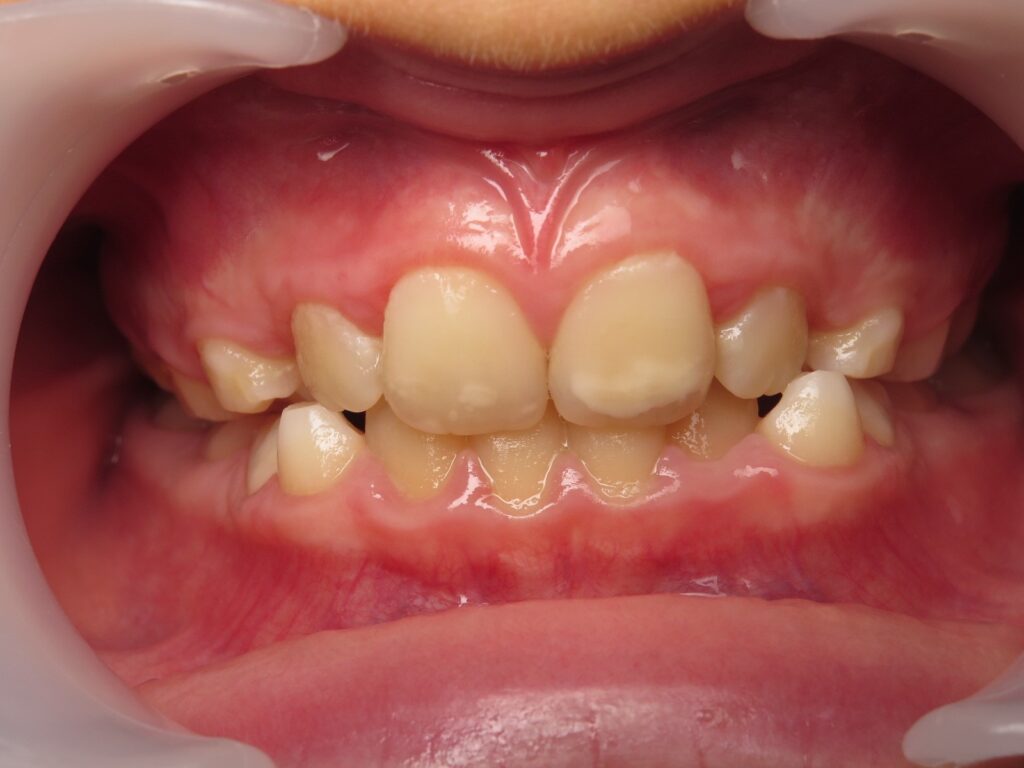

Un cas de recouvrement trop important avec bruxisme sévère :

La photo intermédiaire permet de voir que la situation en denture mixte était bien plus favorable qu’au départ. Quelle dentition aurait eu ce patient si on l’avait traité seulement à 12 ans ? et toutes les tensions dans son corps qui accompagnent ce genre de cas auraient surement perturbé sa croissance générale.

Photos à 6 ans, 9 ans et 15 ans